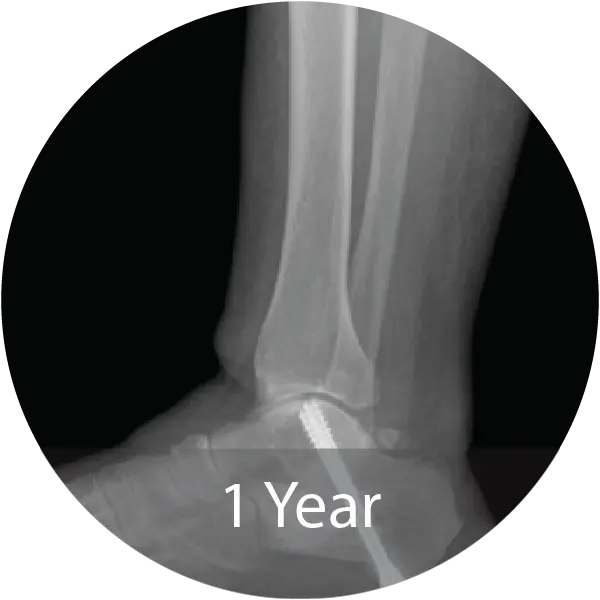

Case of 64-year-old female with hindfoot arthritis treated with tibiotalocalcaneal arthrodesis and intramedullary nailing using InduceXT®. Reported solid osseous consolidation with no postoperative complications, pain-free ambulation, and full return to activities.